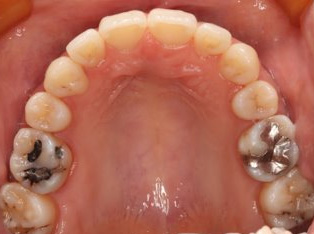

乱ぐい歯、でこぼこがとても酷い状態になります。歯が前後的に重なってしまっている、八重歯になっているなどがこのジャンルに入ります。

顎の大きさと歯の大きさのギャップが大きく、時には歯を抜かないと矯正治療ができない場合もあります。当院では治療期間が長くなるが抜かない治療方針など、一つの治療プランだけでなく、さまざまな可能性の治療方針を説明させて頂くよう心掛けております。こういった考え方はインフォームド・チョイスと言われ近年大切にされている考え方と言われております。

治療前

治療終了前